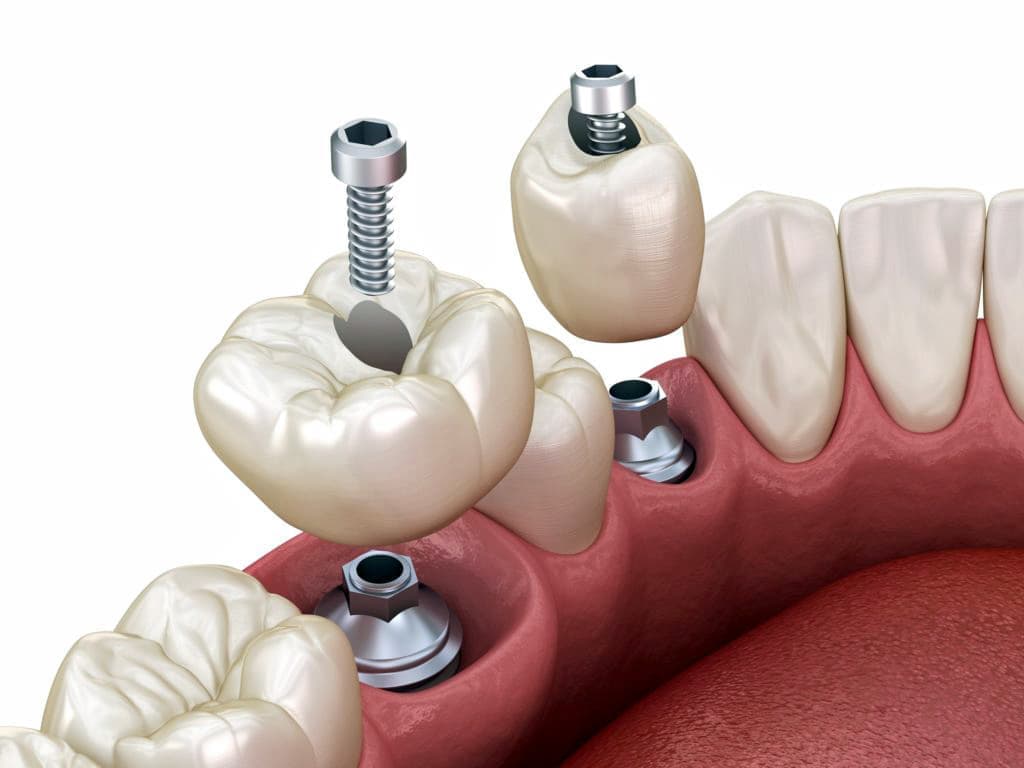

インプラントとは、顎の骨に人工歯根となる金属を埋め込み、その金属を土台にして、天然の歯と同じような人工の歯を取り付ける治療方法です。

埋め込む金属に生体との親和性が高いチタンが使われる事が多く、チタンは長年の臨床研究でインプラントの素材として最も安全であり、また顎の骨としっかり結合することが確認されています。

天然歯のような見栄えだけでなく、これまでの入れ歯やブリッジでは満足することが難しかった「食べる・話す」という機能も回復できます。